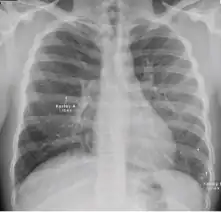

1. Infiltrate or consolidation - Opacification of airspaces within the lung parenchyma. Consolidation or infiltrate can be dense or patchy and might have irregular, ill-defined, or hazy borders.

Dense homogenous opacity in right, middle and lower lobe of primary pulmonary TB. -

Chest x-ray showing patchy opacification on the upper right and mid-zone lung with fibrotic shadows, as well as bilateral hilar lymphadenopathy. -

Chest x-ray showing coarse reticulonodular densities on the lower right lung of post-primary pulmonary TB. -

Chest x-ray of Ghon's complex of active tuberculosis